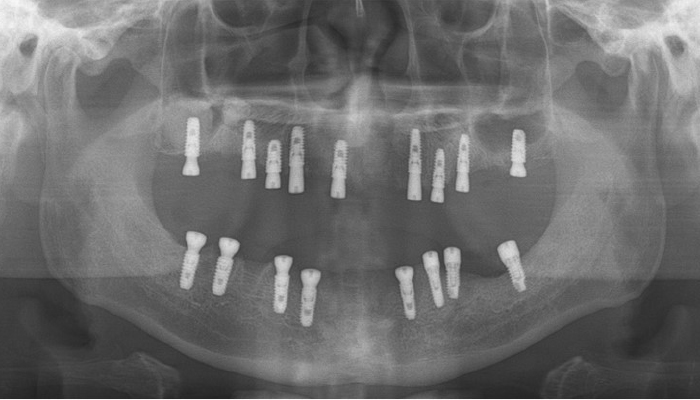

틀니 임플란트 전후 사례

• 식립 전

식립 후